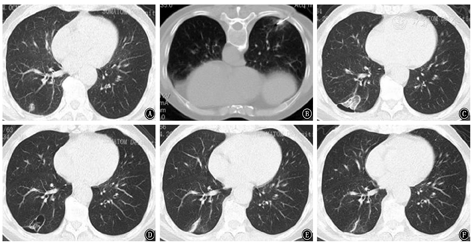

近年来,陆续有介入消融技术治疗GGN型肺癌的报道。RFA治疗GGN型肺癌的2年总生存率、CSS分别可达95.8%、100%[22]。MWA治疗GGN型肺癌也获得令人满意的生存获益,3年无局部进展生存率可达98%,3年CSS率可达96%[23];而且,MWA在多发GGN型肺癌的治疗中也有报道,中位随访18个月内未见肿瘤复发[24]。AHC治疗GGN型肺癌也有少量报道,一项回顾性研究纳入14例接受AHC治疗的GGN型肺癌患者,2年随访期内未见肿瘤复发[25]。这些研究报道中均未发生严重并发症。本中心也对部分GGN型肺癌患者进行了消融治疗,典型病例见图2。